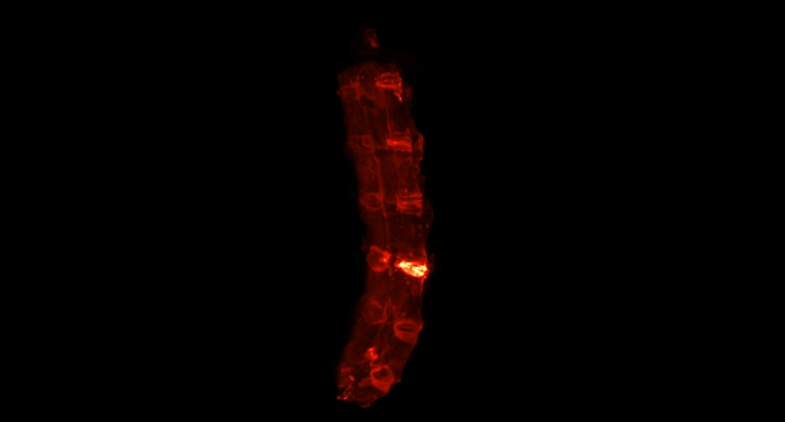

小鼠损伤腰椎的荧光三维成像。荧光信号最高的区域为被损伤的椎间盘,组织中的胶原蛋白被大量破坏。